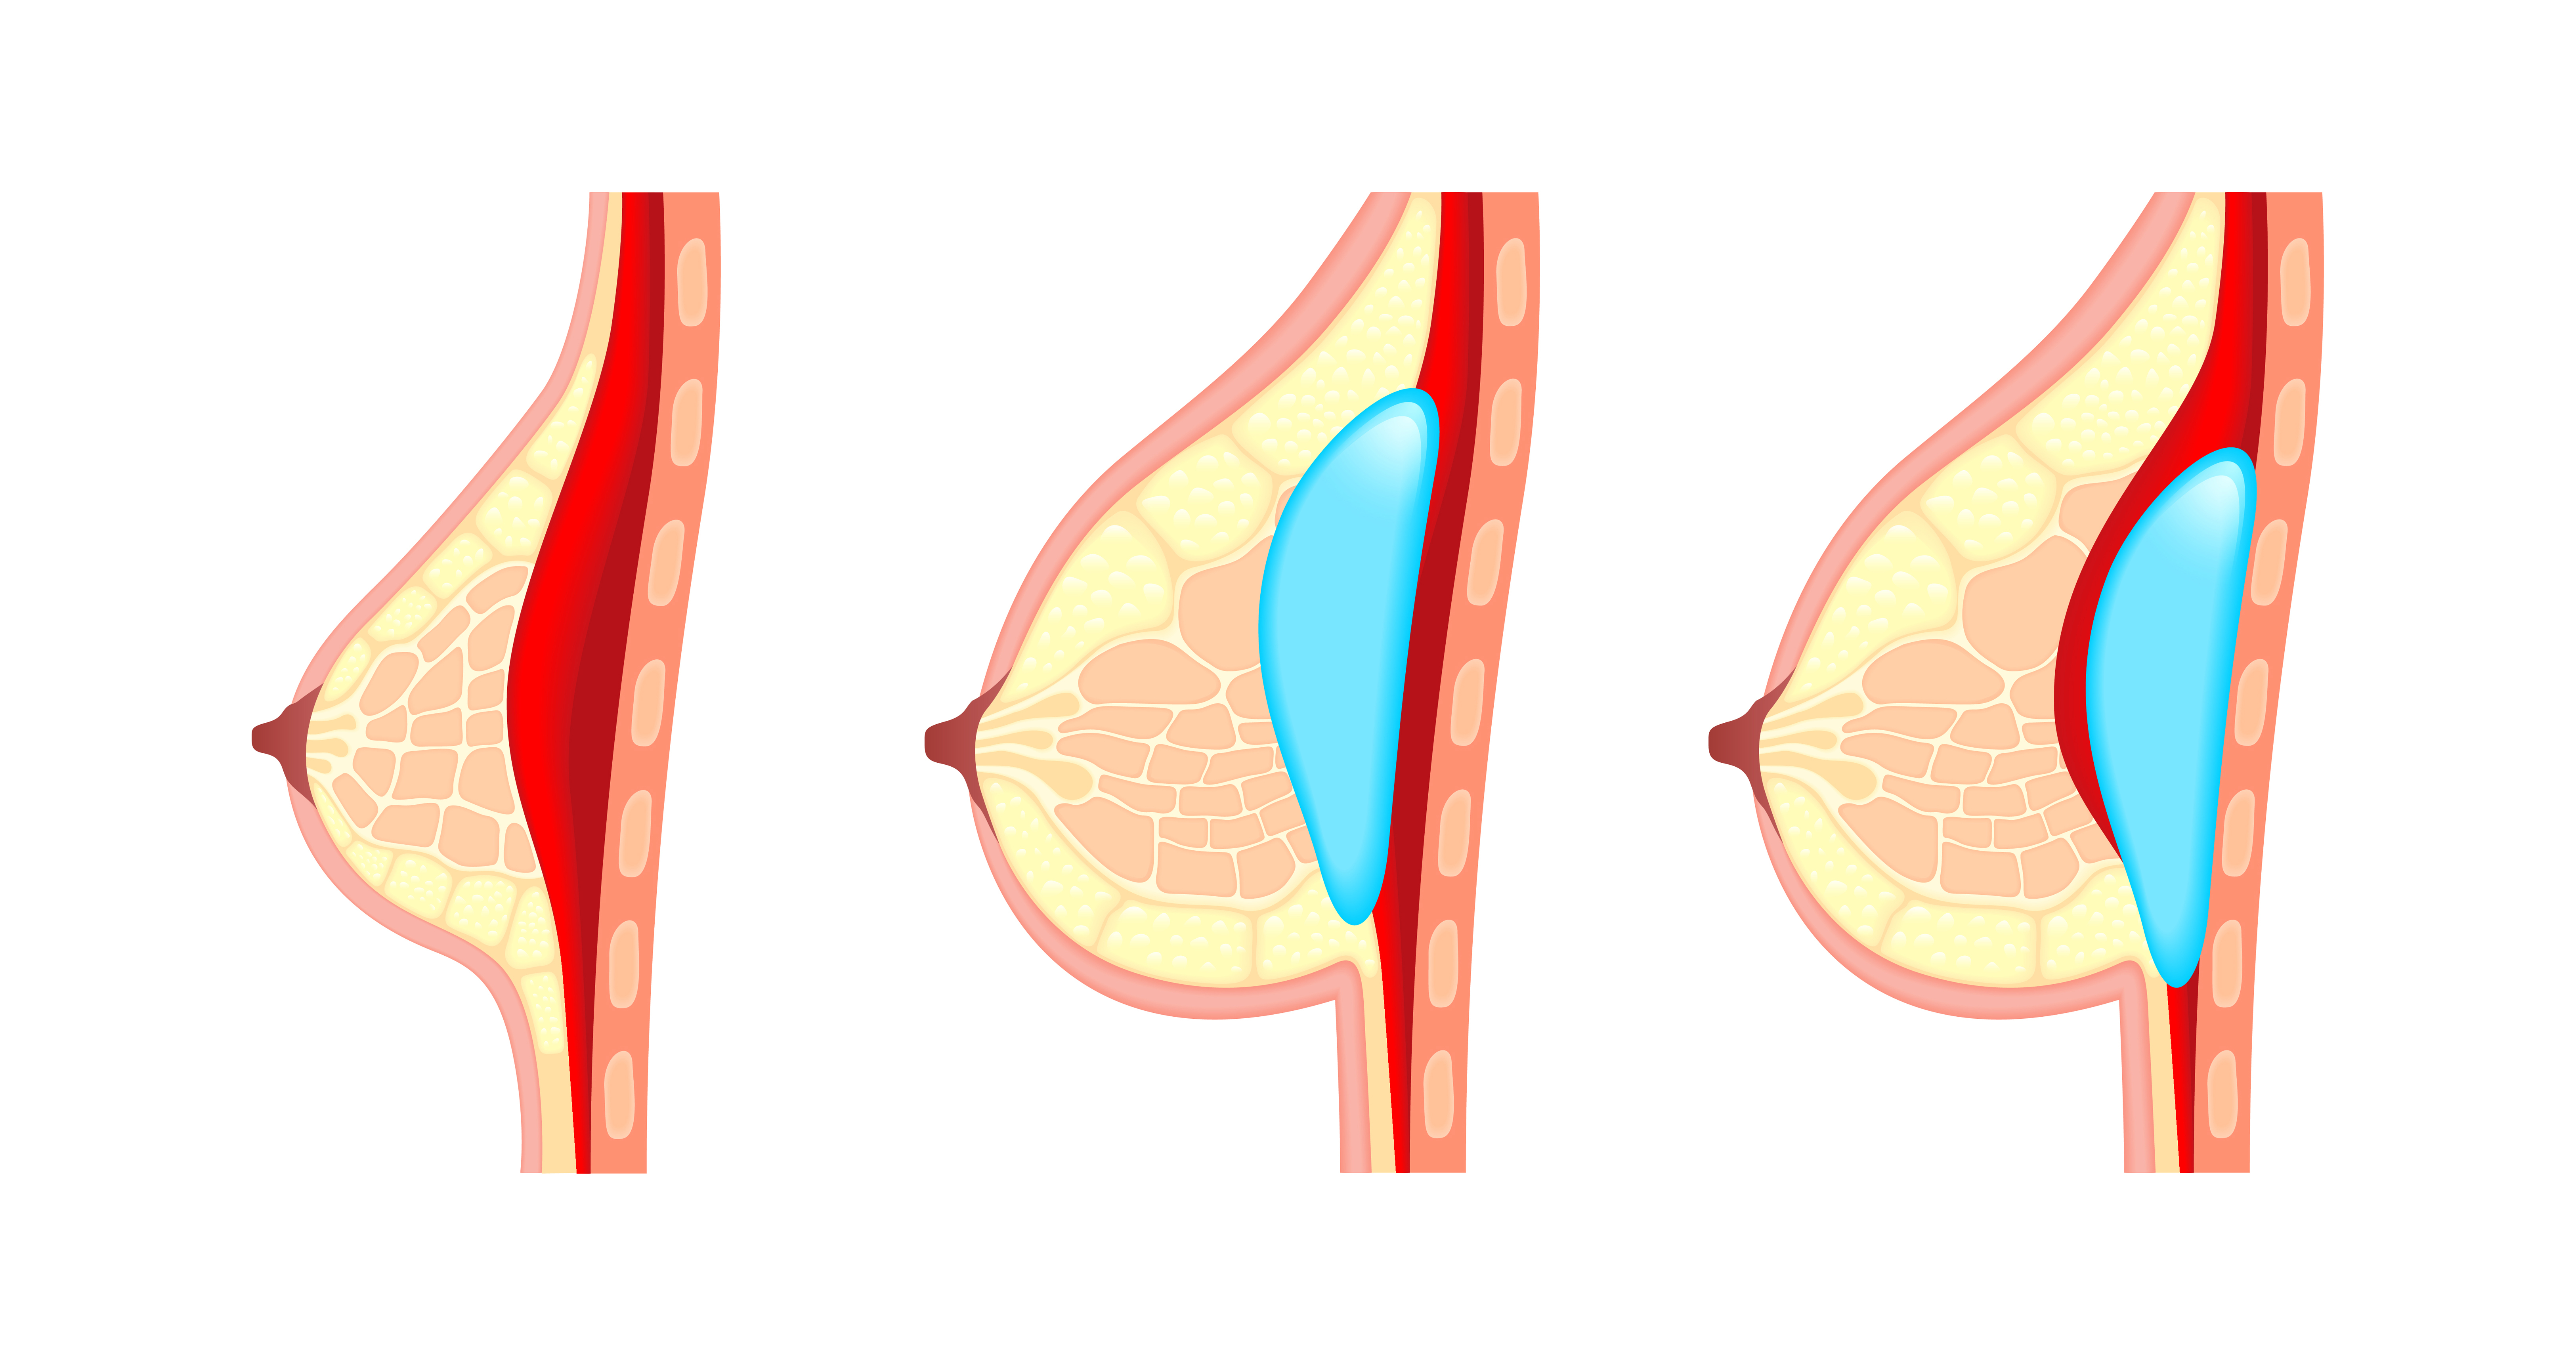

Step 3. Inserting and placing the breast implant

After the incision is made, a breast implant is inserted depending on the type of implant, degree of enlargement desired, your body type and your surgeon’s recommendations.

Step 3. Inserting and placing the breast implant

After the incision is made, a breast implant is inserted depending on the type of implant, degree of enlargement desired, your body type and your surgeon’s recommendations.

What are the different Shapes?

Saline & Silicone Gel implants are typically round, while gummy bear implants come in shaped and round options. Round implants will typically achieve a fuller upper pole (the top portion of your breast), while shaped implants lend a gently sloping look to your breast profile. Both can look very natural with a skilled cosmetic surgeon’s help.